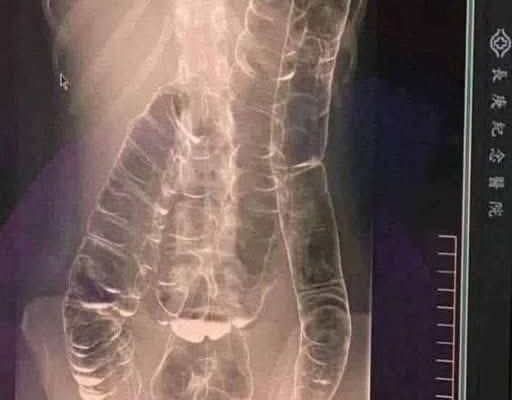

This is an X-ray image of a young woman who suffered from chronic constipation. One day, after experiencing continuous symptoms for over two weeks, she went for a medical check-up and received the X-ray results shown below…

A young woman suffering from years of chronic constipation experienced a severe decline in her condition when she went more than two weeks without a bowel movement. Concerned about her worsening symptoms, she finally sought medical attention, only to receive alarming news.

When waste accumulates in the colon due to an inefficient digestive system, it causes severe discomfort and bloating. Over time, the colon expands beyond its normal size, struggling to contain the excessive buildup of feces. In this case, medical imaging revealed a severely distended colon that had enlarged so much it reached up toward the chest, dangerously close to the heart. The stretching had nearly erased the colon’s natural folds and wrinkles, essential for its proper function. Left untreated, this condition could have led to life-threatening complications.